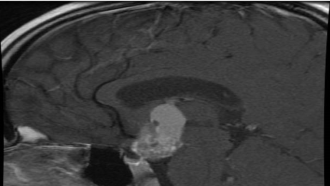

• Los craneofaringiomas son tumores benignos  que crecen en la base del cerebro cerca de la glándula pituitaria.

Estos tumores son más comunes en niños de 5 a 10 años, aunque también pueden aparecer en adultos mayores de 50 años. De hecho, casi la mitad de todos los craneofaringiomas se desarrollan en personas menores de 20 años.

Craneofaringioma

• Síntomas: Aunque el craneofaringioma es un tumor benigno, puede ejercer una presión excesiva sobre el cerebro y causar fuertes dolores de cabeza, problemas de visión y vómitos. El daño a la glándula pituitaria puede conducir a problemas hormonales, que van desde la sed excesiva al crecimiento enlentecido, entre otros síntomas. Pueden comprimir la hipófisis y producir alteraciones de la secreción hormonal.

Diagnostico:

• Pruebas de imagen- Resonancia magnética confirma el diagnóstico y sirve para valorara  el tamaño y la extensión del tumor.

Tratamiento: En el Hospital 12 de Octubre el tratamiento quirúrgico de elección  para los craneofaringiomas de la base del cráneo es el Abordaje Endoscópico Endonasal (AEE). Esta técnica innovadora y mínimamente invasiva utiliza la nariz y las cavidades paranasales como corredores naturales para acceder a tumores de difícil acceso o inoperables previamente. Aunque el objetivo de la cirugía es la eliminación total del tumor con preservación de la función pituitaria, en algunos casos la proximidad del craneofaringioma a las estructuras críticas del cerebro (el hipotálamo, el quiasma óptico y los vasos sanguíneos) hace imposible la resección completa.

El abordaje endonasal ampliado ofrece una mejor vista de la superficie inferior de los nervios ópticos, el quiasma y el tallo pituitario.